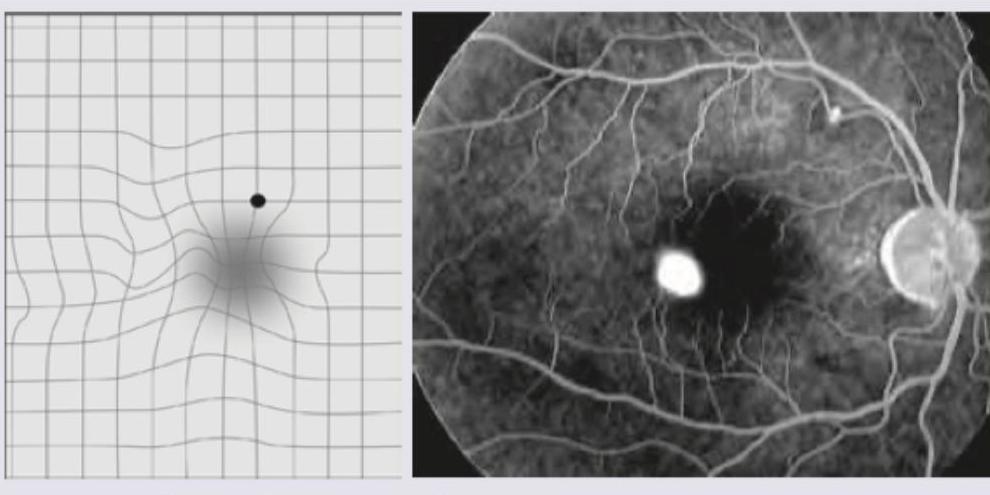

A 20-year-old college student has visual complaints represented in the image given below. FFA of the patient shows presence of:

Explanation: ***Central serous retinopathy*** - The FFA image shows a classic **inkblot or smokestack pattern of leakage** due to choroidal fluid seeping through a defective retinal pigment epithelium, characteristic of central serous retinopathy. - The Amsler grid on the left exhibits **metamorphopsia** (wavy lines) and a **central scotoma** (blurred dark area), indicating macular involvement, consistent with fluid accumulation under the retina in CSR. *Cystoid macular edema* - This condition typically presents with **petaloid leakage patterns** on FFA, due to fluid accumulation within the intraretinal layers, which is not seen here. - While it can cause metamorphopsia and reduced vision, the characteristic "inkblot" leakage on FFA points away from CME. *Age-related macular degeneration* - This condition is more common in older individuals, whereas the patient is a **20-year-old college student**. - Wet AMD typically shows **choroidal neovascularization (CNV)** with associated leakage or bleeding, which is distinct from the serous detachment and RPE leak seen. *Central retinal venous occlusion* - CRVO is characterized by widespread **retinal hemorrhages**, dilated and tortuous veins, and cotton wool spots due to impaired venous outflow. - FFA in CRVO would show delayed venous filling, capillary non-perfusion, and possible neovascularization, none of which are evident in the provided images.